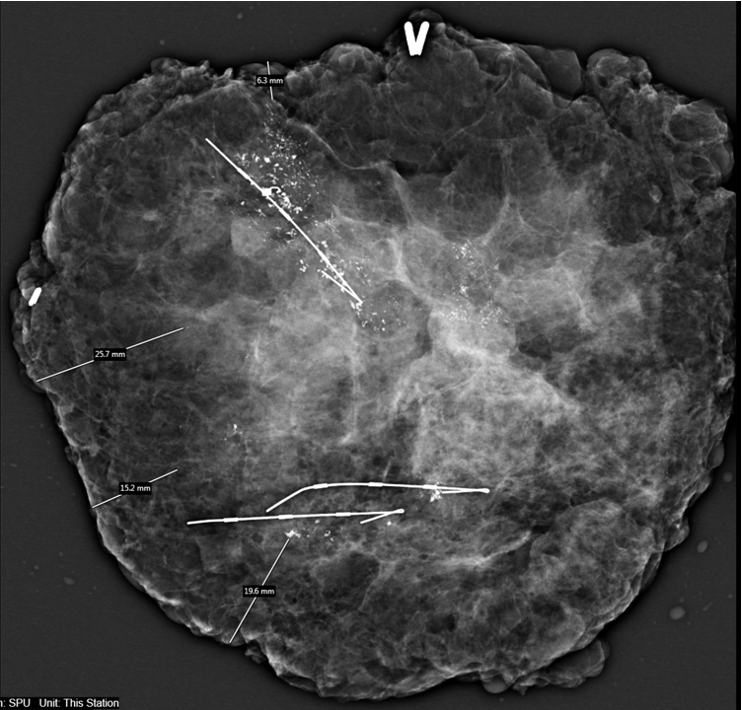

术前我院钼

靶提示:左乳癌治疗后,左乳可见多发簇状、区域性分布粗糙不均质钙化,范围较大者位于上方,范围为4.3×1.8cm。

术前钼钯